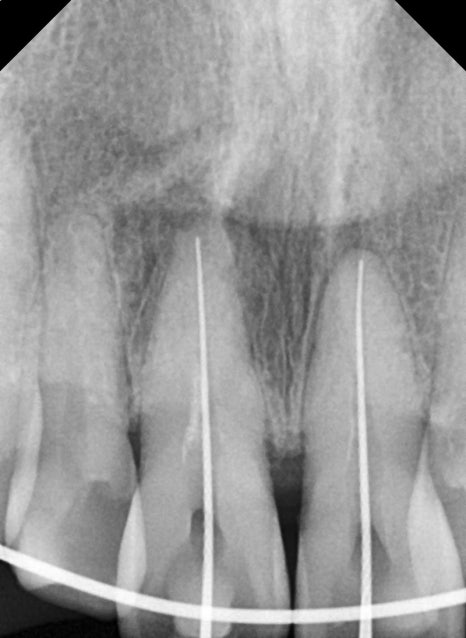

For this patient as well,

the panoramic X-ray and CT scan clearly confirmed

an alveolar bone fracture around the two front teeth and tooth displacement.

Immediate professional stabilization was needed.

After the recovery period, root canal treatment for the front teeth

Teeth that have received a strong impact

may develop sensitivity, pain, or discoloration weeks to months later.

This is due to nerve damage.

For this patient as well, the possibility of nerve necrosis in the two front teeth was confirmed,

and after accurate working length measurement,

root canal treatment was performed.